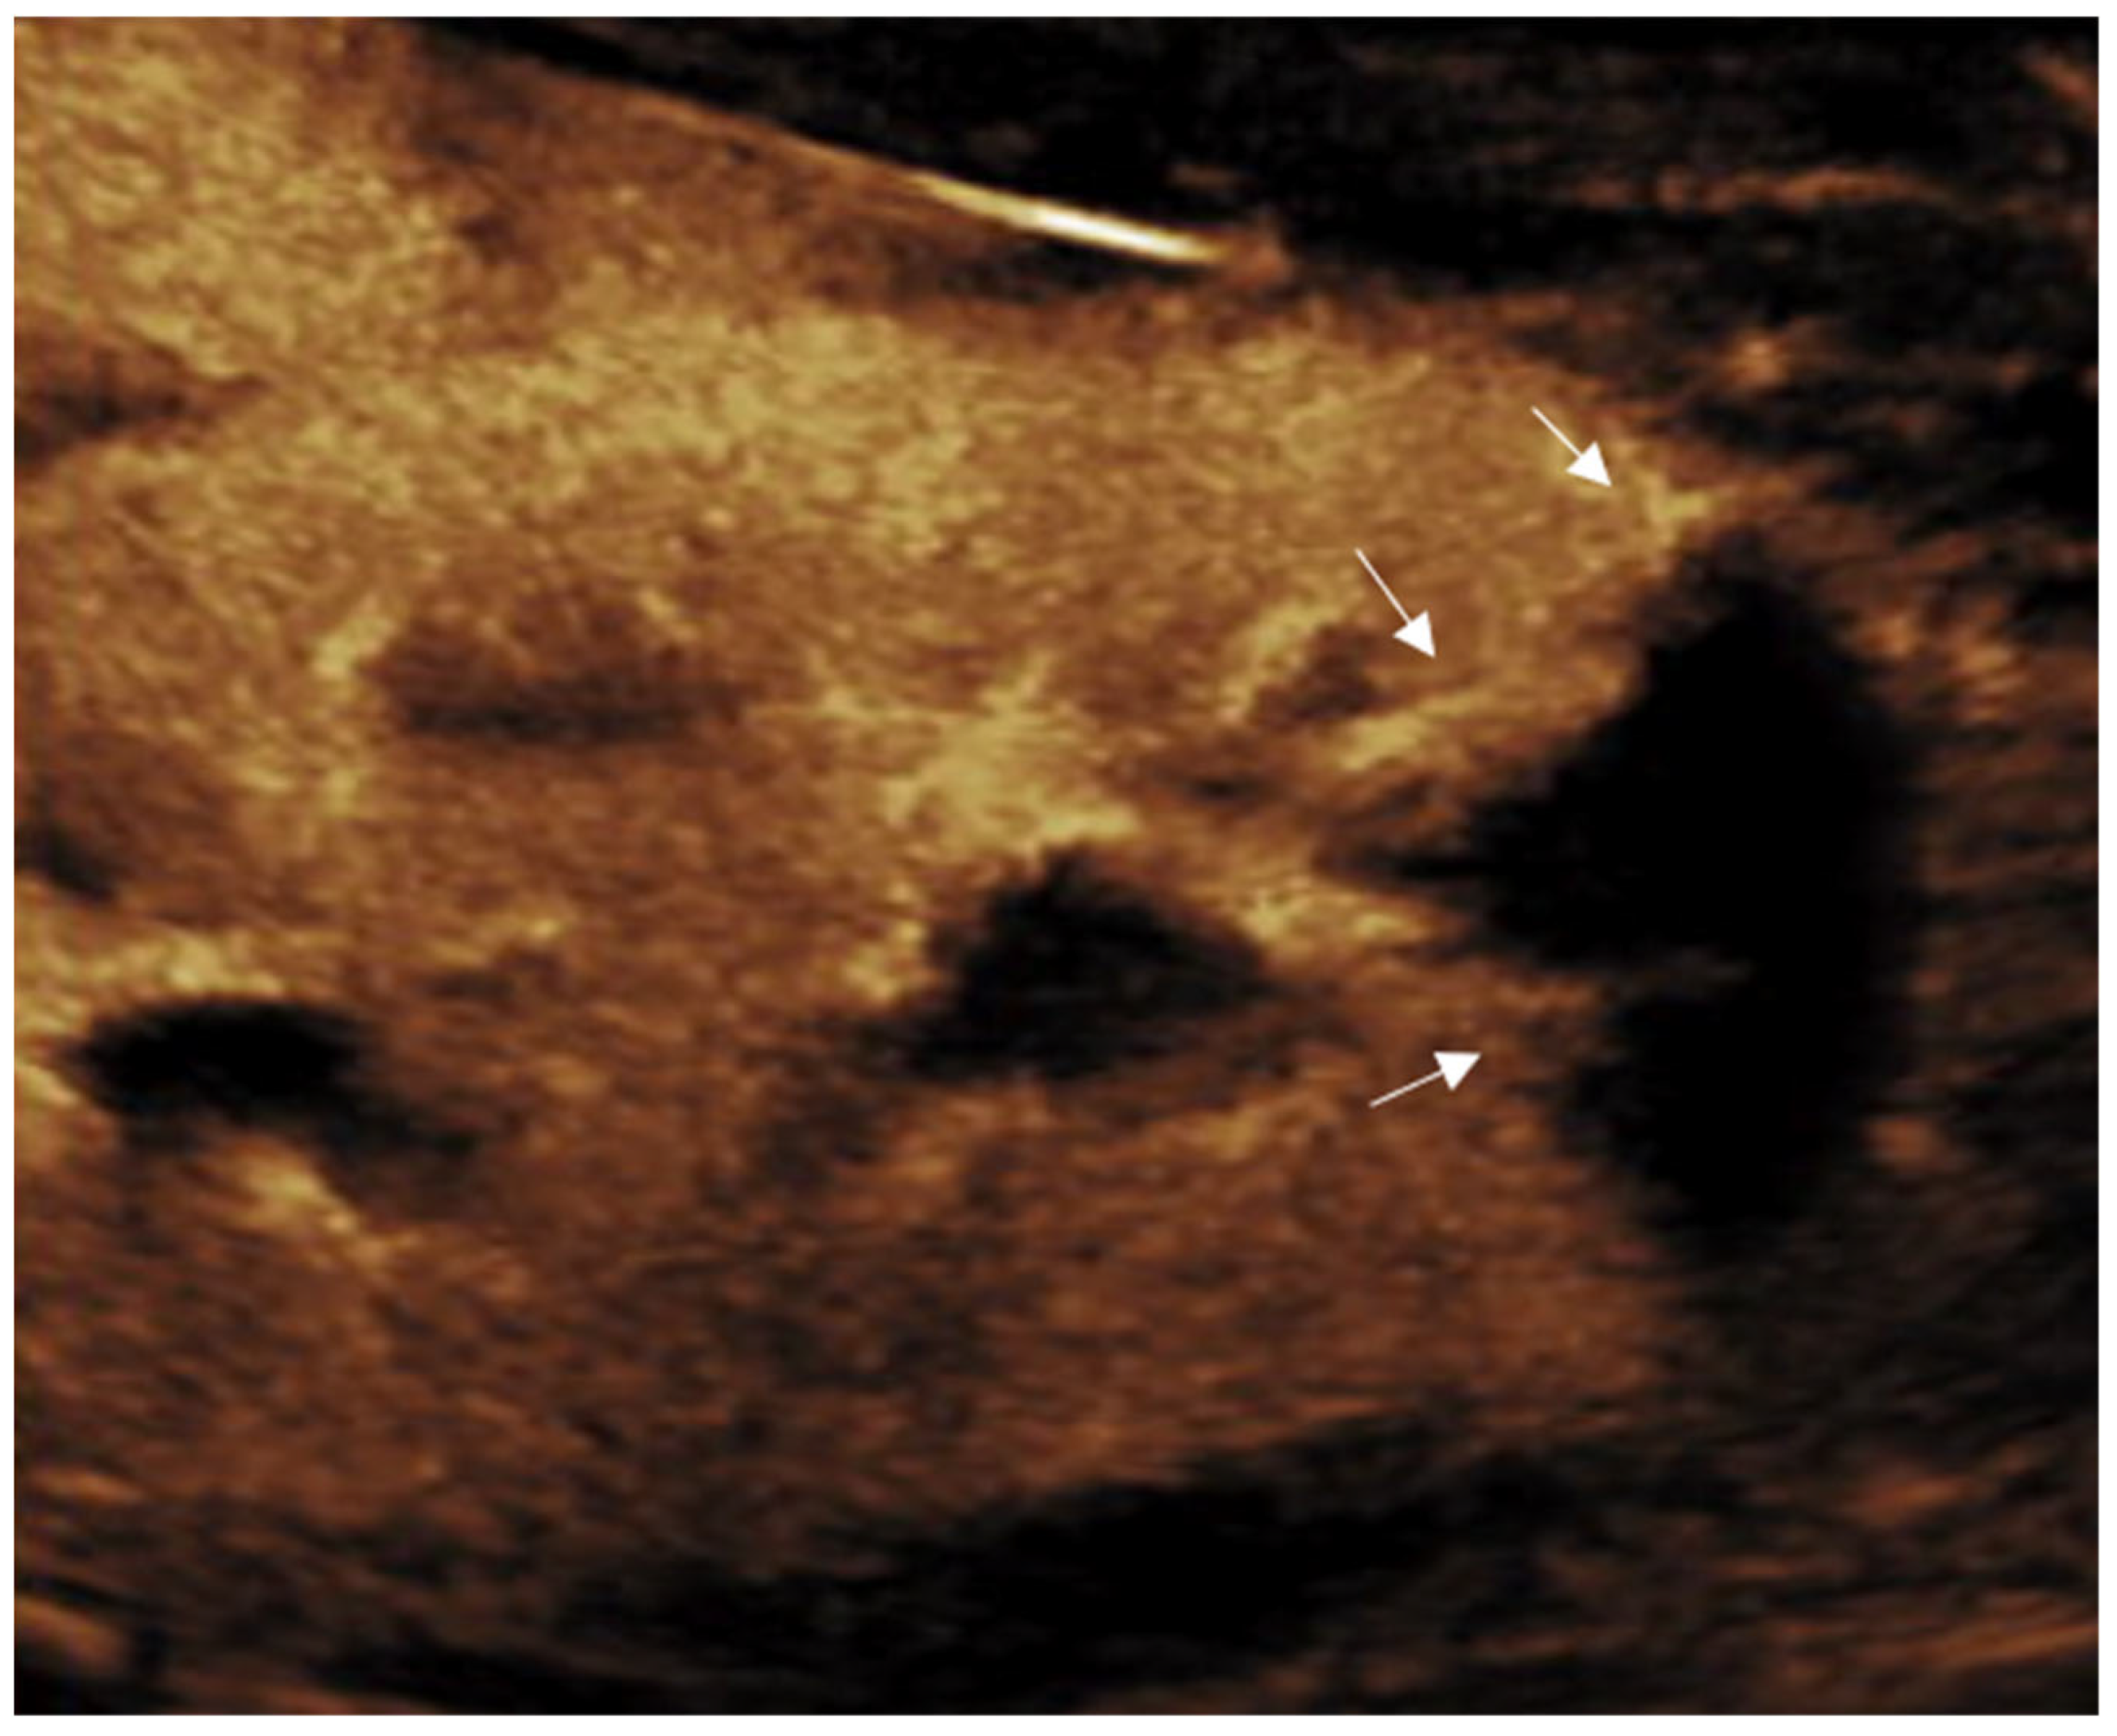

- Pšeničny, E.; Glušič, M.; Pokorn, M.; Ključevšek, D. Contrast-enhanced ultrasound in detection and follow-up of focal renal infections in children. Br. J. Radiol. 2022, 95, 20220290. [Google Scholar] [CrossRef]

- Jung, H.J.; Choi, M.H.; Pai, K.S.; Kim, H.G. Diagnostic performance of contrast-enhanced ultrasound for acute pyelonephritis in children. Sci. Rep. 2020, 10, 10715. [Google Scholar] [CrossRef]

- Rinaldo, C.; Grimaldi, D.; Di Serafino, M.; Iacobellis, F.; Verde, F.; Caruso, M.; Capasso, R.; Esposito, M.; Romeo, V.; Imbriaco, M.; et al. An update on pyelonephritis: Role of contrast-enhanced ultrasound (CEUS). J. Ultrasound 2023, 26, 333–342. [Google Scholar] [CrossRef]